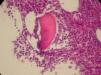

However, other alterations were found during a routine appointment in the Rheumatology Department including anemia (hemoglobin: 7.2g/dL), low hematocrit (22.6%), high ferritin levels (732mg/dL), positive direct coombs test, and elevated total and indirect bilirubin. By protein electrophoresis, the total protein was elevated (11.8g/dL), the albumin/globulin ratio was low (0.50), the albumin was low (3.94g/dL) and the gamma globulin was high (6.25g/dL) with a monoclonal component. The patient was referred back to the hematology department and diagnosed with hypergammaglobulinemia and AIHA at which time a bone marrow biopsy was performed that identified MM (Figures 1 and 2).